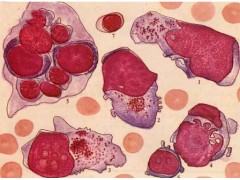

恶性黑色素瘤,A375

【产品商标】ATCC

【供应限制】仅供科研使用